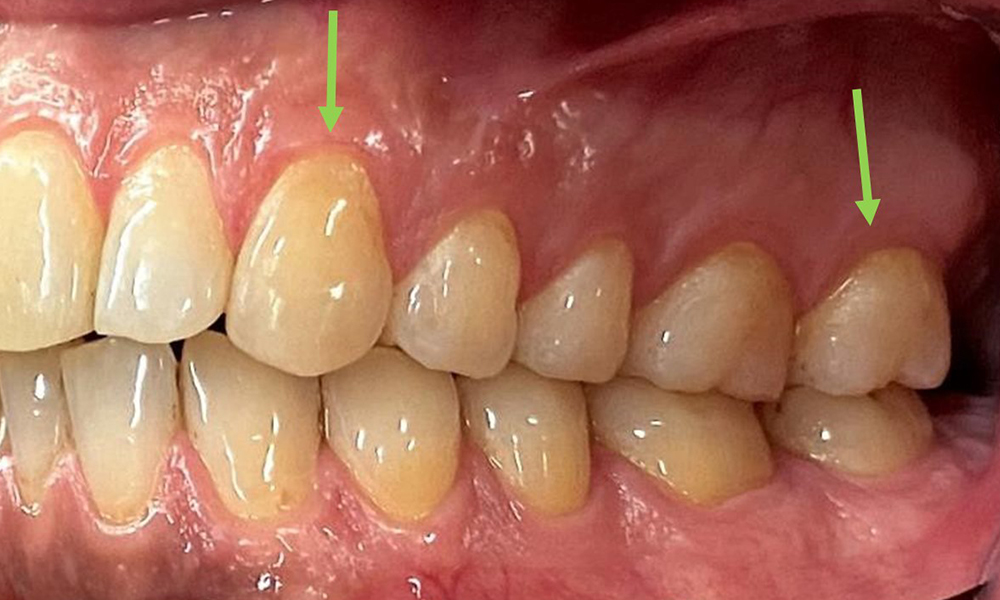

Close-up view of teeth

Fig. 5: Close-up view of teeth 45 to 47. The green arrows show dental attrition and erosions of the buccal cusps with partial enamel loss, © Dr R. Krapf

Dental findings

The patient has full dentition with a total of 28 teeth. There were noteworthy erosions and attritions. (Fig. 4, Fig. 5). Due to bruxism, the patient has been wearing a splint with an adjusted bite block at night for many years. The erosions were caused by long-term consumption of isotonic beverages. No periodontal bone loss or active caries were observed.